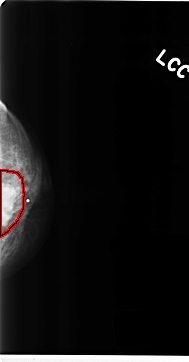

C_0141_1.LEFT_CC

LEFT_CC LINES 4696 PIXELS_PER_LINE 2448 BITS_PER_PIXEL 12 RESOLUTION 50 OVERLAY

FILE: C_0141_1.LEFT_CC.OVERLAY

TOTAL_ABNORMALITIES 1

ABNORMALITY 1

LESION_TYPE MASS SHAPE IRREGULAR MARGINS MICROLOBULATED

ASSESSMENT 5

SUBTLETY 5

PATHOLOGY MALIGNANT

TOTAL_OUTLINES 1

BOUNDARY